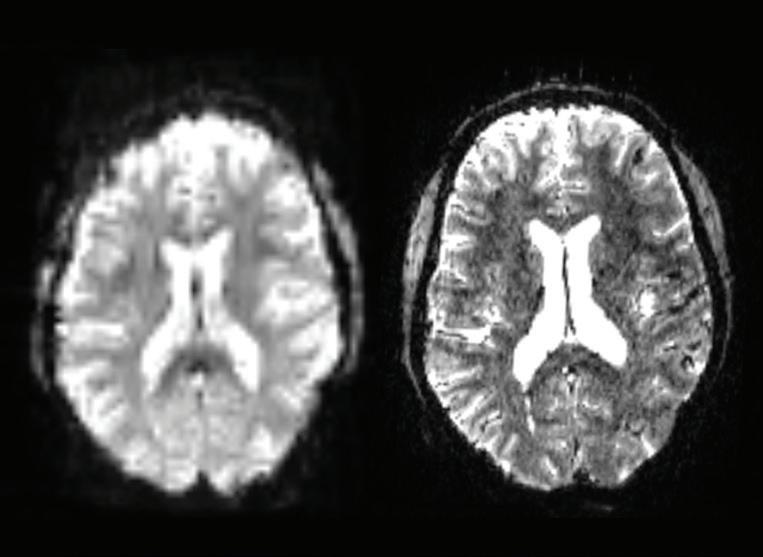

Dr. Murrough’s team uses ultra-high field 7-Tesla magnetic resonance imaging (MRI) to better understand how neural networks communicate and influence one another—as well as how these interactions underlie pathological brain states such as major depressive disorder. The scans at left demonstrate this dramatically enhanced resolution as compared to standard MRI imaging, an advance that provides clearer modeling of the brain’s functional and structural networks. Image courtesy of Yael Jacob, PhD, Director, the Brain Networks and Cognition (BNC) Lab at Mount Sinai